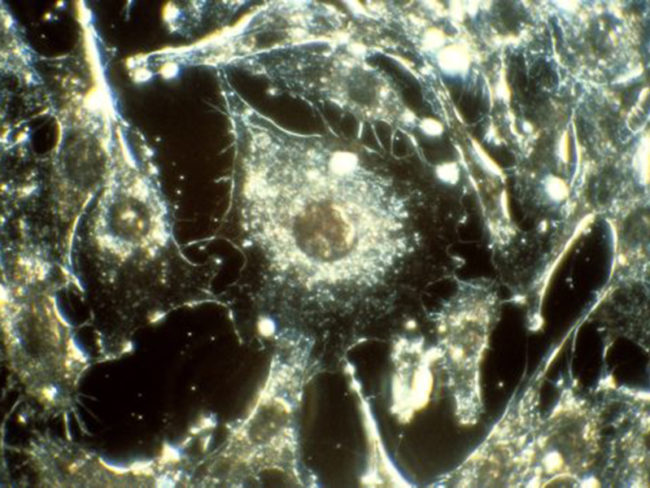

Российские ученые исследовали уникальное вещество, отключающее защиту раковых клеток от химиотерапии, сообщает РИА «Новости». Соединение уже опробовали на раке прямой кишки. По словам специалистов, использование подобных средств позволит не только повысить эффективность лечения, но и снизить дозировку химиотерапии. Ирина Гужова из Института цитологии РАН и ее команда предложили блокировать в раковых опухолях действие особых ферментов,…